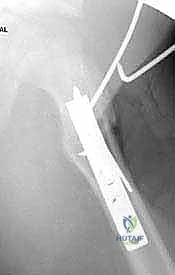

6. إدخال الشريحة والتثبيت (Plate Insertion & Fixation)

يتم إدخال نصل الشريحة ذات الزاوية 90 درجة في المسار الذي تم تحضيره في عنق الفخذ. ثم يتم ضم جزئي العظم المقطوعين معاً (إغلاق الفجوة)، مما يؤدي فوراً إلى تغيير زاوية عنق الفخذ إلى الوضع الطبيعي الجديد. يتم تثبيت الجزء الطويل من الشريحة على جسم عظم الفخذ باستخدام براغي قوية من التيتانيوم أو الفولاذ الطبي المقاوم للصدأ.

لماذا الشريحة ذات الزاوية 90 درجة (90-Degree Blade Plate) تحديداً؟

قد يتساءل البعض: لماذا يصر الأستاذ الدكتور محمد هطيف على استخدام هذا النوع المحدد من الشرائح في عمليات قطع عظم الفخذ الداني التقويمي؟ الإجابة تكمن في الميكانيكا الهندسية:

- التثبيت فائق الصلابة (Rigid Fixation): النصل العريض للشريحة الذي يدخل في عنق الفخذ يوفر ثباتاً دورانياً وزاوياً لا مثيل له، مما يمنع العظمة من التحرك أثناء فترة الالتئام.

- التحكم الدقيق في الزوايا ثلاثية الأبعاد: تسمح هذه الشريحة بتصحيح زاوية الميل (Varus)، وكذلك تصحيح الدوران الخاطئ للعظمة (Derotation) في نفس الوقت.